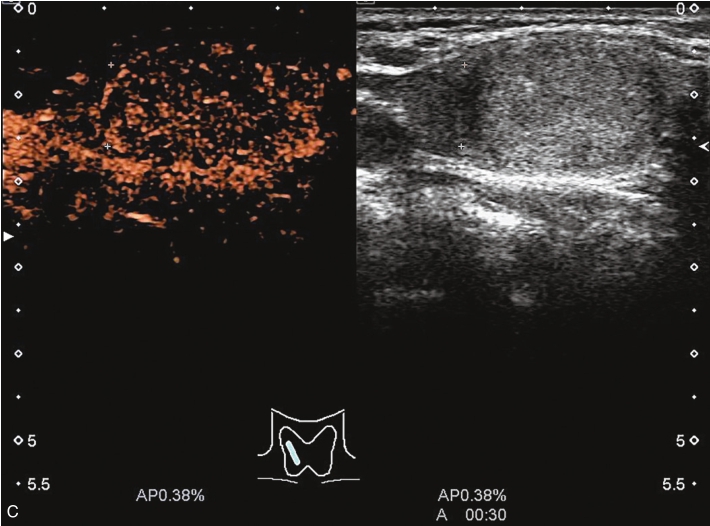

甲状腺左叶上极较大结节增强早期呈稍高增强,自结节外周向中央灌注,增强晚期呈等增强,结节内部可见不均匀低增强区,见图1-3-8、ER1-3-4。

图1-3-8 结节性甲状腺肿超声造影图像

ER1-3-4 结节性甲状腺肿的超声造影

甲状腺左叶中部结节15s开始增强。增强早期与周围正常甲状腺组织呈同步等增强,内部增强不均匀,增强后结节边界清,形态规则,周边可见环状高增强,增强晚期呈不均匀性低增强,见图1-3-10、ER1-3-5。

结节性甲状腺肿超声造影表现为病变多与周围正常甲状腺组织呈同步等或高增强,增强多较均匀,伴有囊性变者,内部可见无增强区,增强后结节边界清,周边可见环状增强,增强晚期呈等或稍高增强,也可呈稍低增强。

图1-3-10 结节性甲状腺肿超声造影图

A.增强早期结节呈同步不均匀性等增强;B.增强晚期呈不均匀性低增强